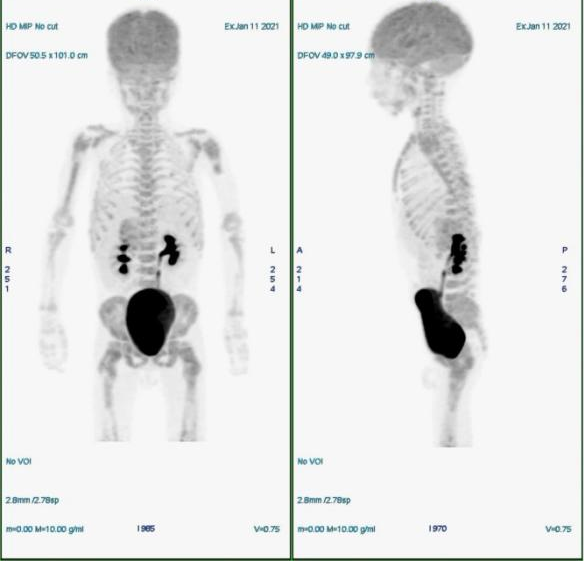

PET/MR(2021.1.11)

腹膜后右侧肾上腺区不规则团块,FDG代谢增高,考虑恶性病变,神经母细胞瘤可能性大,建议结合病理;腹膜后腹主动脉右旁数枚肿大淋巴结,FDG代谢增高,考虑转移;全身骨骼FDG代谢弥漫性增高,考虑骨髓浸润。

治疗后评估:2021.11.10MR(类PET成像)提示全身骨多发异常信号。

放疗后复查:2021.12.21PET/MR:术区未见明确肿块,FDG代谢未见明显异常;全身多处骨骼局部骨质信号异常,FDG代谢未见异常增高,考虑骨转移治疗后改变。